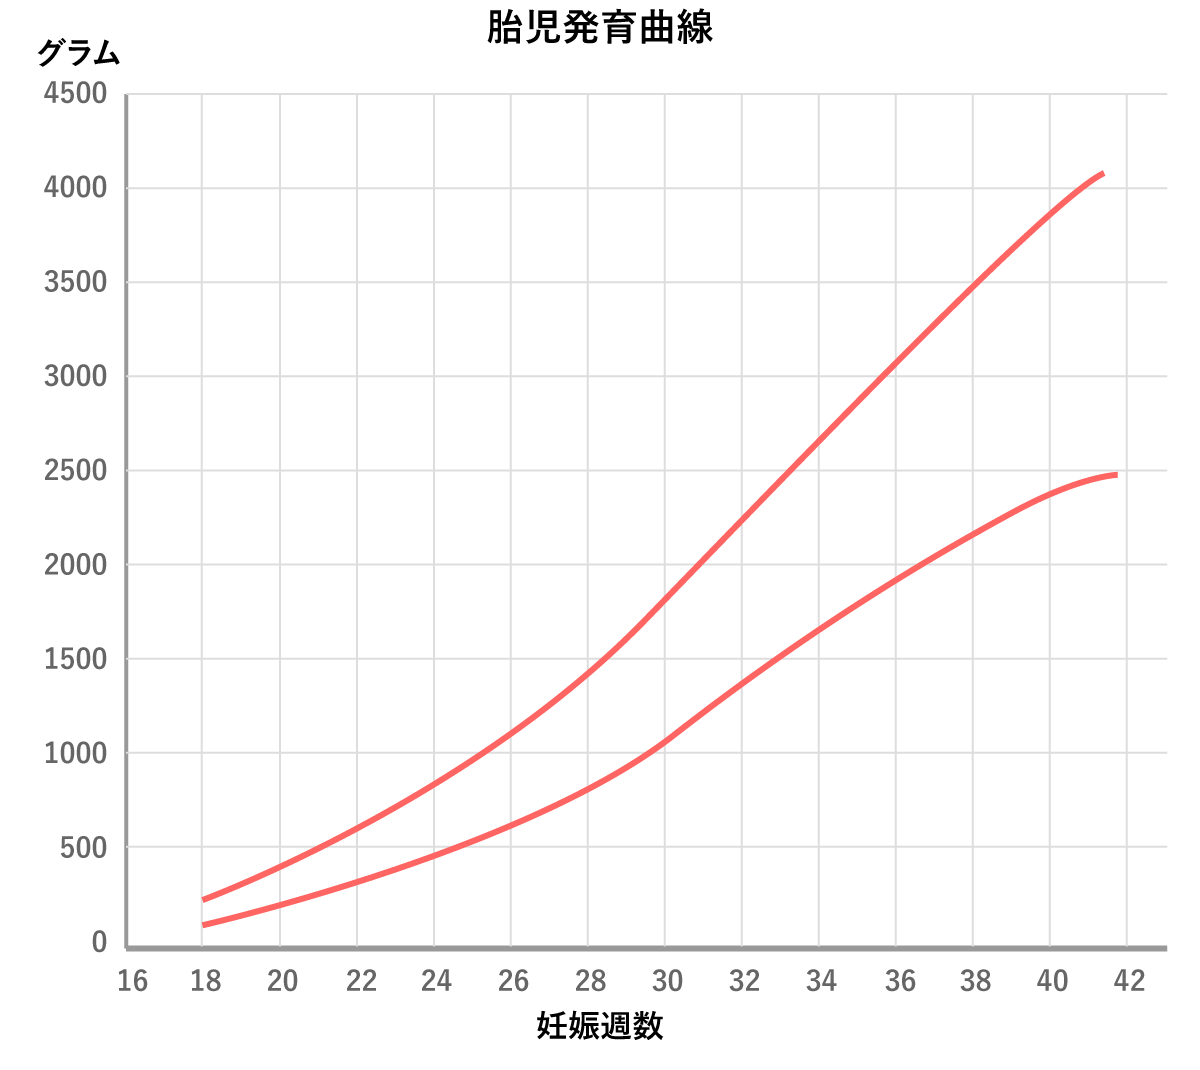

母子手帳「胎児発育曲線 新生児の成長曲線 」の見方と活用法-おむつのムーニー 公式 ユニ・チャーム。

医師監修 胎児の発育曲線 成長曲線 とは?どのように見ればいいの?ゼクシィBaby。

胎児発育曲線ギリギリ成長の小ささで16週から34週まで育ってるべびお君。 - 保育士うたのサイト。

胎児発育曲線』とは?週ごとの発育の目安を助産師が解説◎ - 株式会社エバーセンス。

胎児発育曲線』とは?週ごとの発育の目安を助産師が解説◎ - 株式会社エバーセンス。

胎児発育曲線の±2.0SDの意味は?エコー写真に学ぶ統計学 - 日常を少し掘り下げてみる。

医師監修 おなかの赤ちゃんの発育は順調? 「胎児発育曲線」とはトモニテ。

胎児発育曲線の±2.0SDの意味は?エコー写真に学ぶ統計学 - 日常を少し掘り下げてみる。

母子手帳「胎児発育曲線 新生児の成長曲線 」の見方と活用法-おむつのムーニー 公式 ユニ・チャーム。